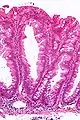

| Micrograph of a sessile serrated lesion. H&E stain. | |

SSLs are diagnosed by their microscopic appearance; histomorphologically, they are characterized by (1) basal dilation of the crypts, (2) basal crypt serration, (3) crypts that run horizontal to the basement membrane (horizontal crypts), and (4) crypt branching. The most common of these features is basal dilation of the crypts.

Unlike conventional colonic adenomas (e.g. tubular adenoma, villous adenoma), they do not (typically) have nuclear changes (nuclear hyperchromatism, nuclear crowding, elliptical/cigar-shaped nuclei).